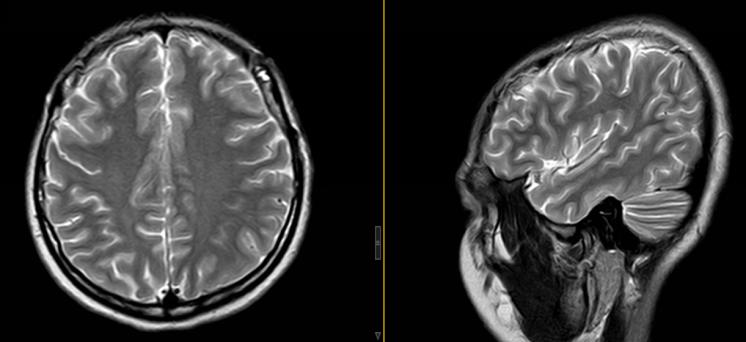

“切除病变前行电生理监测,可见癫痫样放电明显;病变切除后复查可见异常放电消失。”吴杰介绍道。术后,祝女士的手脚感觉正常、活动灵活,没有出现手术并发症,住院一段时间后便顺利拆线出院。

▲术后MRI:占位已完整切除